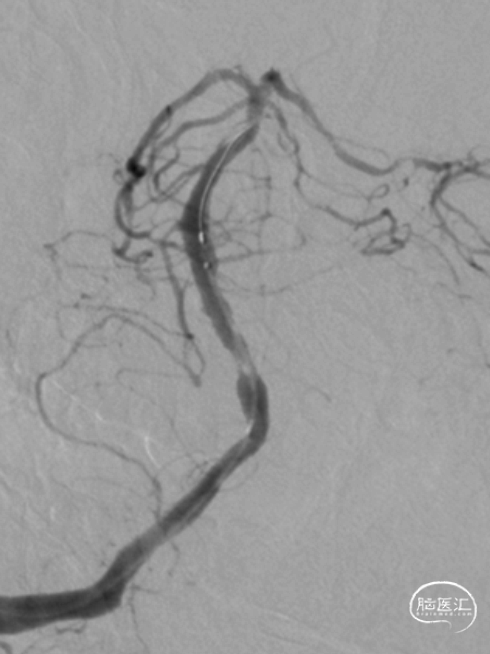

分别应用2.5mm×15mm、3.25mm×15mm球囊,仔细定位后,以6ATM命名压缓慢扩张。

沿微导丝送入XT-27微导管至基底动脉远端,退出微导丝,送入Neuroform EZ 4.0mm×20mm颅内支架,准确定位后释放于狭窄处。观察支架位置良好,残余狭窄轻。

最后影像:椎基底动脉连接处残余狭窄约20%,前向血流改善明显,mTICI3级。远端各血管显影良好,分支较术前增多。